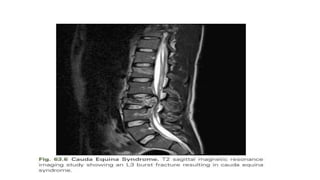

Cauda Equina Syndrome

• The cauda equina is defined as the region of the neuroaxis occupied

by the filum terminale.

• The only neurological structures in this region include the lumbar and

sacral roots.

• Injuries in this location are typically a pure LMN injury.

• Findings often include:

absent bulbocavernosus reflex

absent deep tendon reflexes

flaccid urinary bladder, and

reduced lower-extremity muscle

tone

• It is differentiated from conus

medullaris syndrome by

the presence of asymmetrical

weakness and the absence of

UMN involvement.

• Like conus medullaris syndrome, burst fracture and fracture-

dislocation are the most common vertebral column injuries

associated with this condition.

• Cauda equina injuries have better recoveries owing to the resiliency

of the roots to injuries and the greater regeneration capacity of the

roots compared with the spinal cord.

• However, the sacral roots are very delicate, and injuries to them may

be permanent.

• In general, cauda equina syndrome in the setting of herniated disk

pathology is treated early (within 24 hours) if possible, to prevent

residual symptoms.

• However, functional outcome in a traumatic setting is similar to conus

medullaris syndrome.

• There is no strong evidence correlating functional outcome to surgical

decompression, nor is there any evidence that suggests cauda equina

injuries fare better with early versus late decompression.